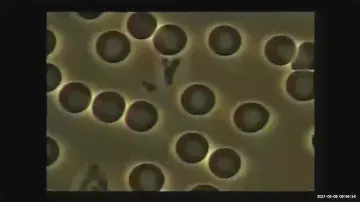

doTERRA Balance essential oil and study effect with red blood cells